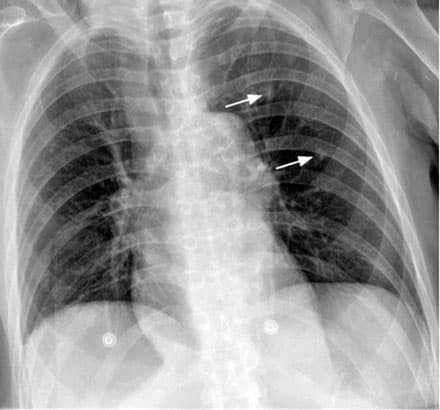

Chest X-ray of a 76-year-old woman with melanoma showing two pulmonary nodules in her left upper lung lobe consistent with metastatic disease.